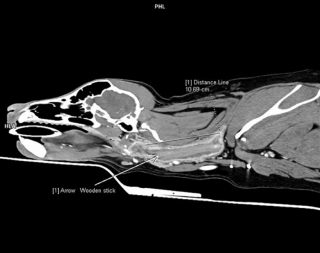

Erika Villedieu, le docteur qui a pris en charge la Labrador, a réalisé un scanner. Celui-ci a révélé la présence d’un corps étranger enfoncé et coincé dans la gorge de Poppy. La chienne a été opérée dans l’urgence. Erika est parvenue à extraire un bâton de bois d’une longueur de 10 cm ! Cela faisait 6 semaines qu’il était dans la gorge de la pauvre chienne.